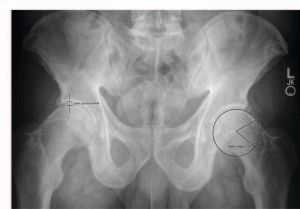

Так выглядит заболевание.

Некроз правого тазобедренного сустава